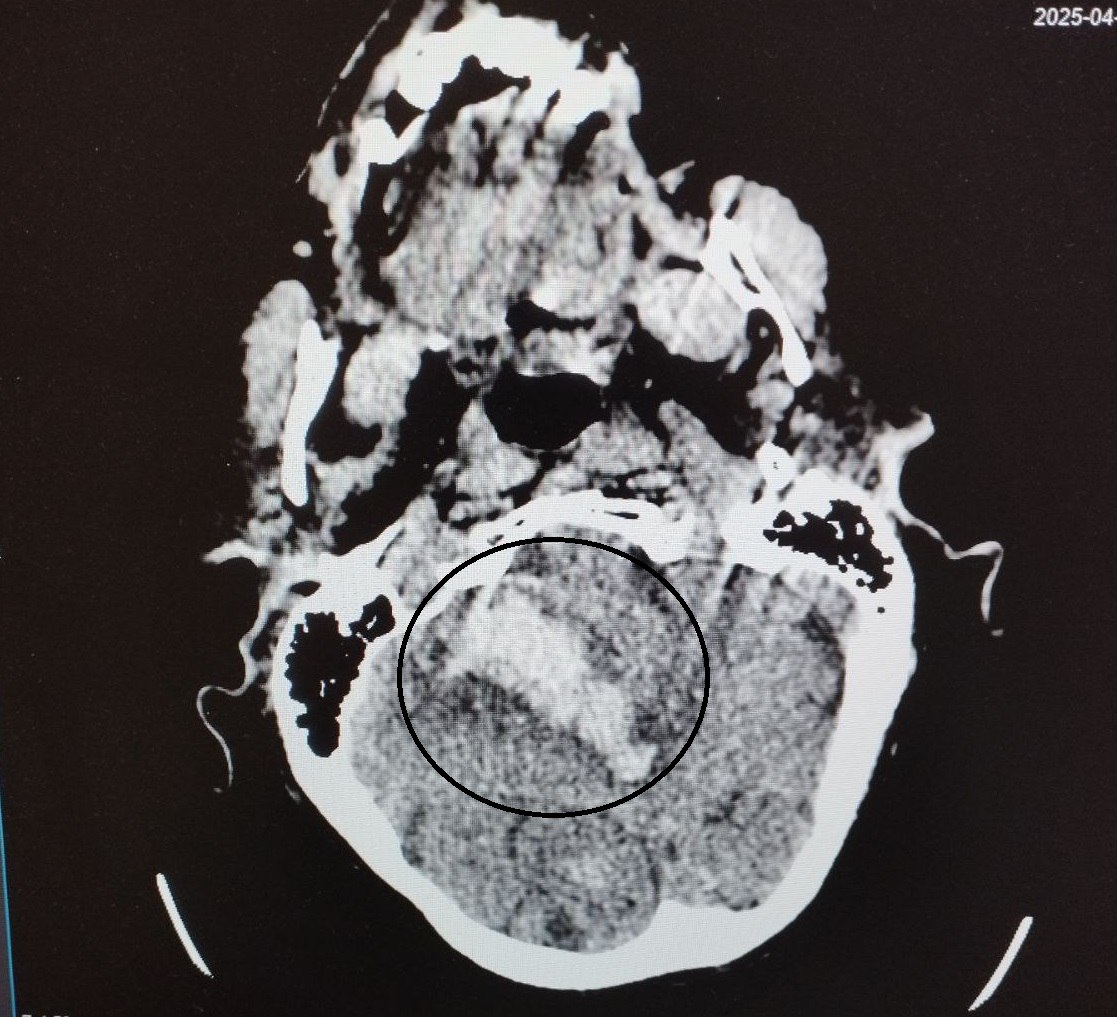

Оперативно оказанная медицинская помощь помогла спасти жизнь 87-летней пациентке, поступившей в апреле в первичное неврологическое отделение БСМП №1 в Воронеже в крайне тяжёлом состоянии. Как сообщили в департаменте здравоохранения Воронежской области, у женщины диагностировали геморрагический инсульт правого полушария мозжечка, осложнённый внутримозговой гематомой, кровоизлиянием в желудочковую систему мозга и стволовые структуры.

В распоряжении медиков имеются томограммы, на которых зафиксированы обширные внутримозговые гематомы и кровоизлияния в области мозжечка и желудочковой системы мозга.

На фото – томогораммы, на которых видны внутримозговые гематомы в области правого полушария мозжечка, в стволе головного мозга, кровоизлияния в желудочковую систему мозга.